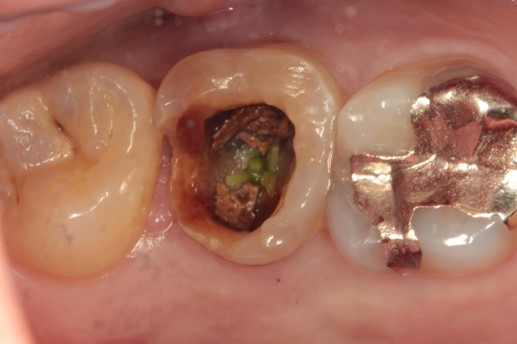

治療前

奥歯に大きな穴が空いてる |

カウンセリング・診断結果 |

現在の歯の状態は保存が非常に難しく、これ以上無理に残すと周囲の健康な骨や隣の歯にまで悪影響を及ぼすリスクが高い状況です。 |